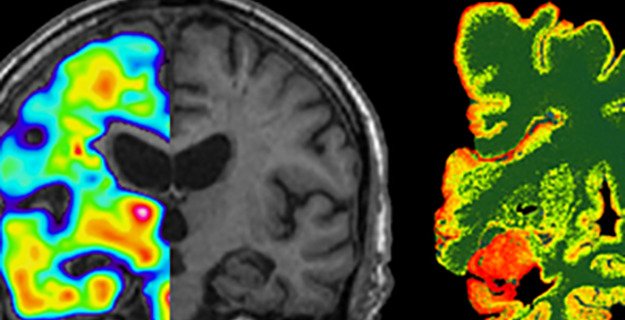

Foto: Agneta Nordberg,Karolinska InstitutetAndrea Varrones forskargrupp

Molekylär hjärnavbildning av neurodegenerativa sjukdomar